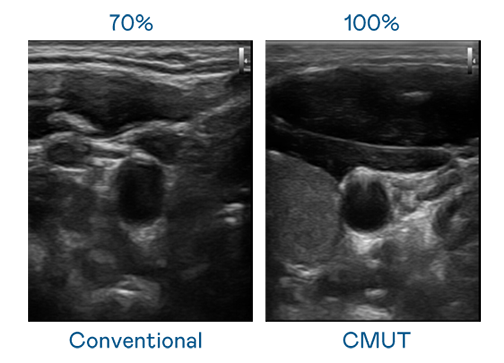

CMUT 技术是一种用电容式微机电元件来产生超音波讯号的技术。与传统 PZT 压电式技术相比,CMUT 频宽增加 30%,更宽频的超音波讯号让影像解析度大幅提升,是实现高影像品质医疗超音波扫描、促进精准医疗发展的关键技术。

超音波影像的解析度高低,首先取决于探头能发出的讯号频宽。雅博 CMUT 可提供高清晰的超音波讯号,提供高频宽、高灵敏度、影像纹理细节更高的超音波影像,协助医护人员缩短影像判读时间及利用精准的医疗影像进行诊断。